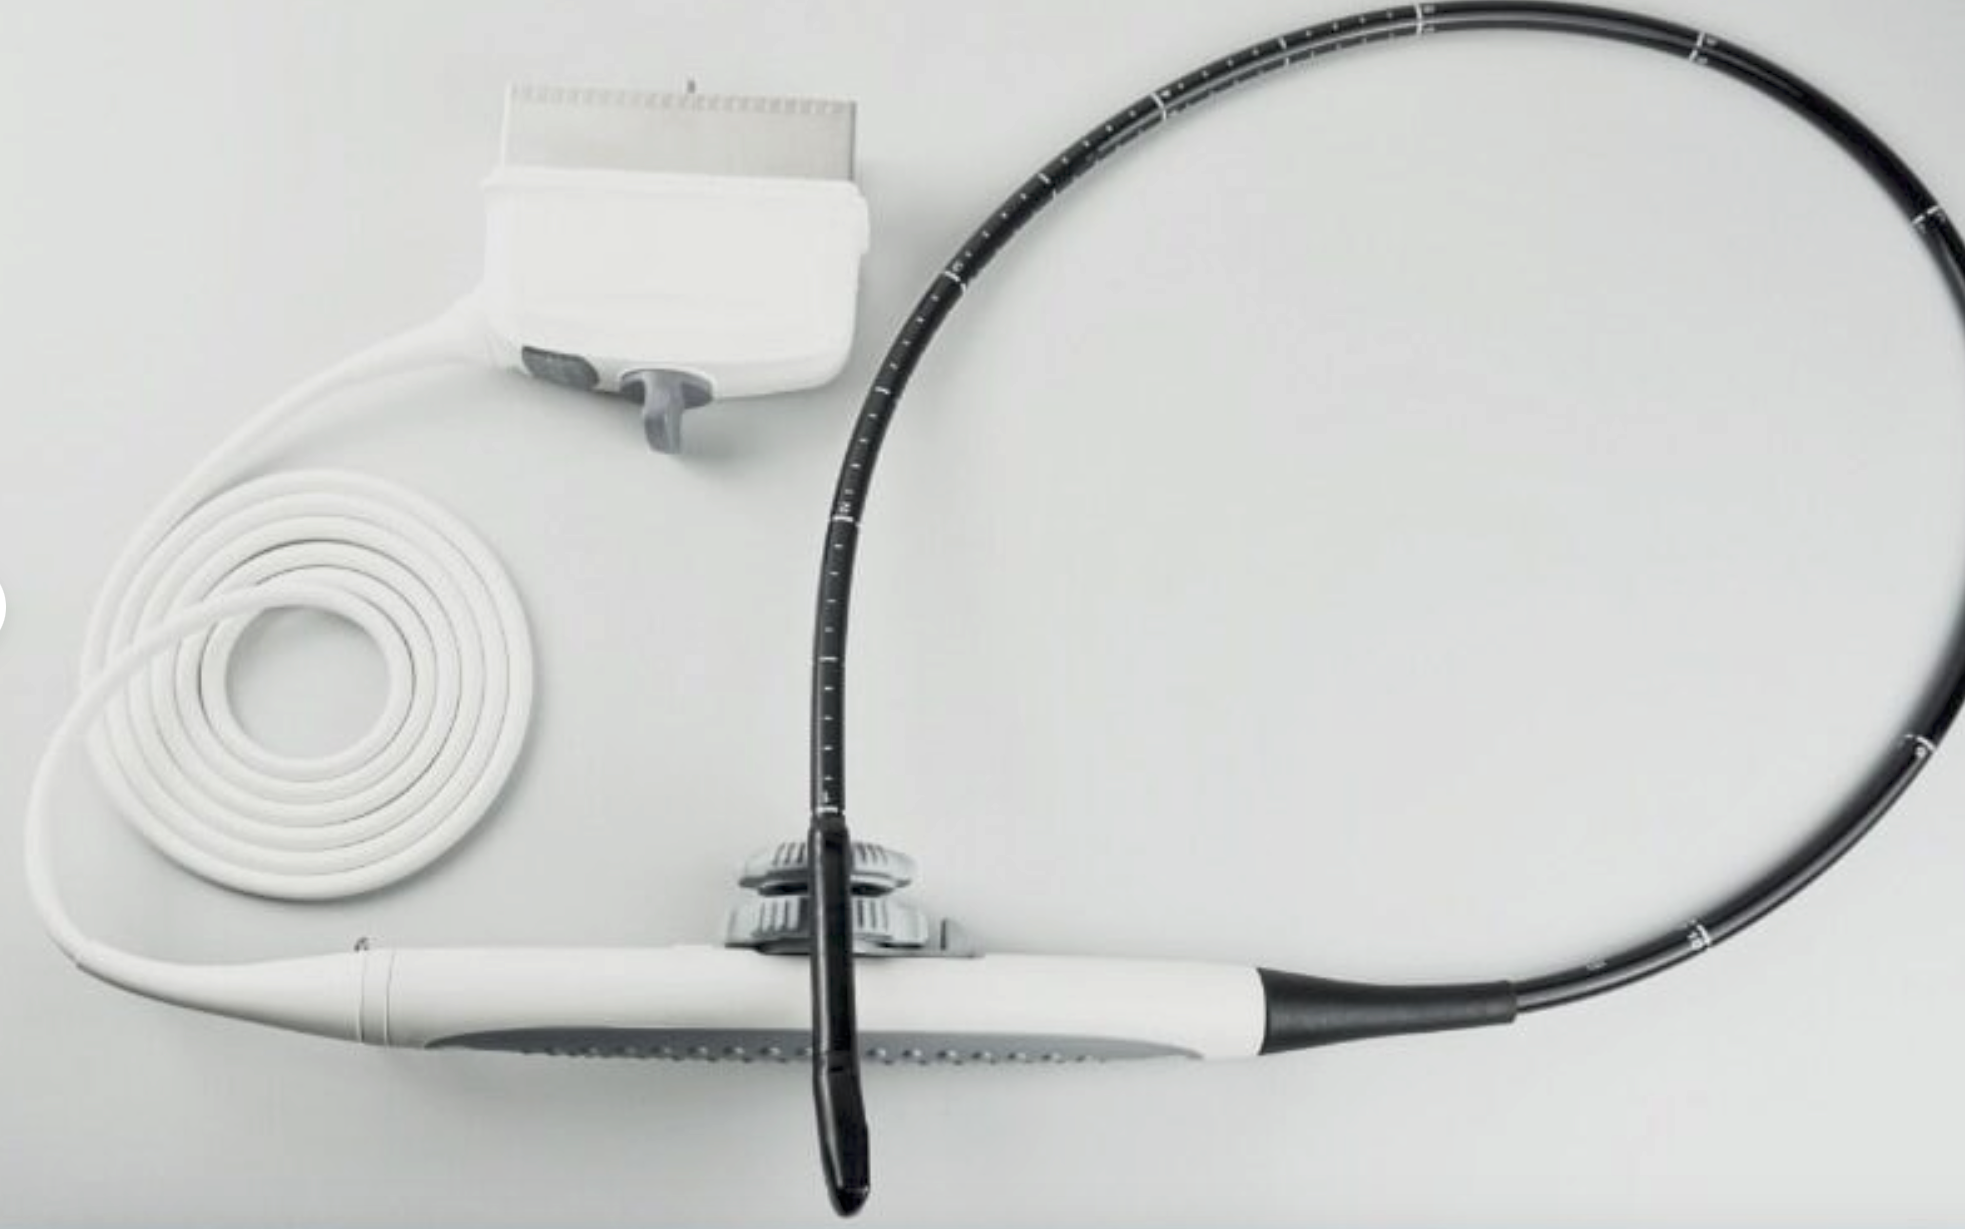

- Die rektale Sonde hat eine Linse von 65 mm und ein langes Kabel.